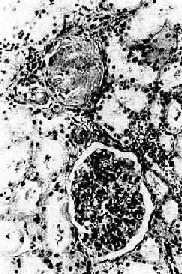

镜检下,肾细动脉硬化明显,小叶间动脉及弓形动脉内膜增厚。依病程而有多少不等的入球动脉及肾小球发生玻璃样变(图8-12)。附近的肾小管由于缺血而萎缩、消失,间质结缔组织增生及淋巴细胞浸润。该处由于肾实质萎缩和结缔组织收缩而形成凹陷的固缩病灶,周围健存的肾小球发生代偿性肥大,所属肾小管亦呈代偿性扩张,使局部肾组织向表面隆起,形成肉眼所见的无数红色细颗粒(由于该处血供良好而呈红色)。

高血压病之肾

图8-12 高血压病之肾

肾小球入球小动脉管壁玻璃样变性,肾小球纤维化,玻璃样变